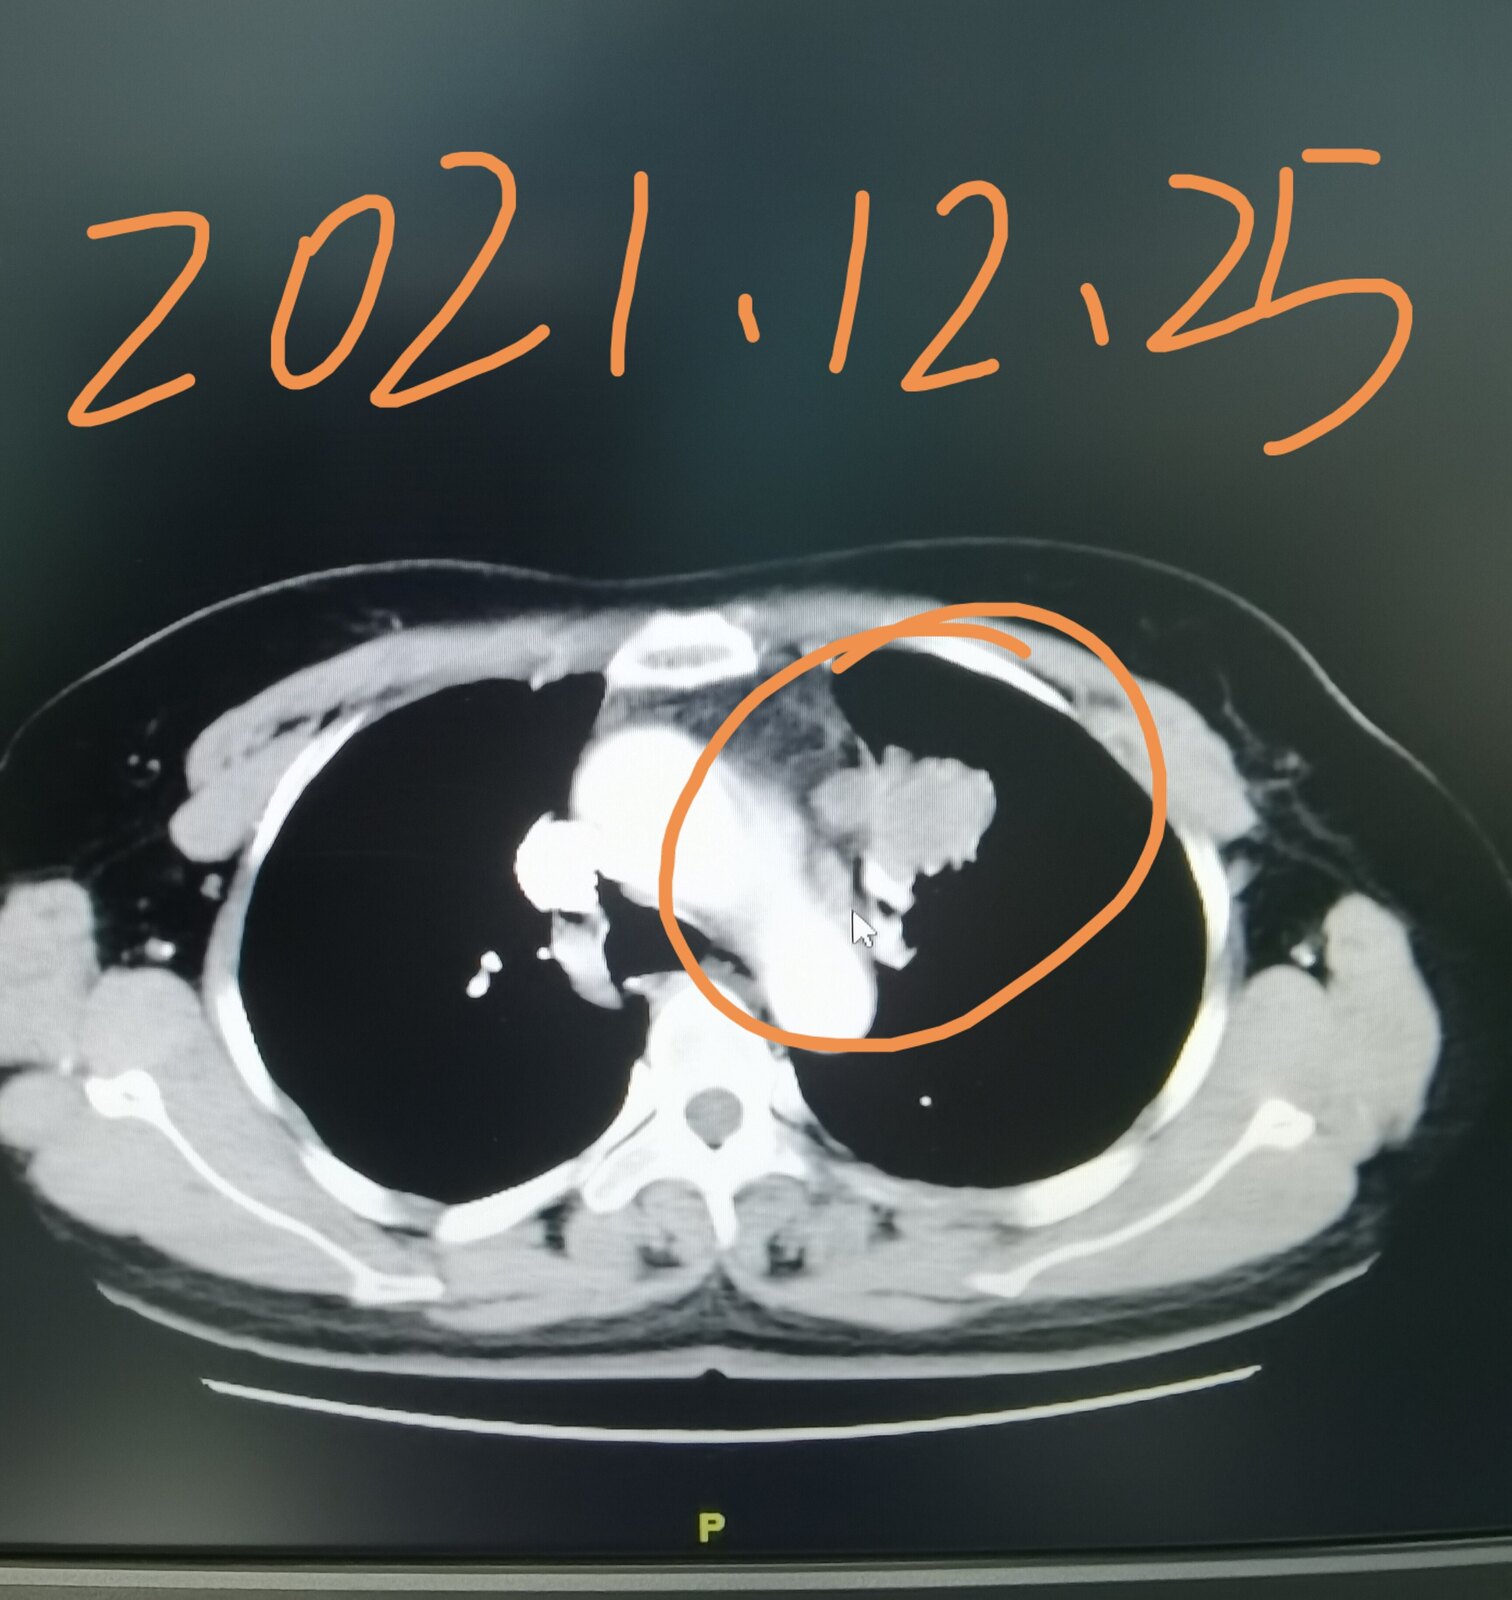

今天有一台手术就属于这个情况,我把这位患者的片子给大家发在下面,这是一位51岁的女士,三个月前因为咳嗽在当地医院拍片子,发现了肺部占位,她过来找我,想在我这里治疗。我给她进行了系统的检查,当时发现左上肺这个占位侵犯了纵隔,纵隔淋巴结增大,考虑转移,直接手术效果不好。这位女士好在其他部位并没有转移,我给她安排了穿刺,病理显示是一个肺腺癌,做基因检测,存在EGFR敏感突变,她吃了两个月的靶向药,肿瘤和淋巴结都缩小了。今天给她做的手术,手术过程是很困难的,里边粘连的比较严重,血管也很难分离,但过程很顺利,现在正在密切观察中。她除了左上肺这个病变之外,左下肺还有一个结节,吃靶向药也没有减小,术中探查的时候,考虑是一个肺内淋巴结,也给她一并切了下来。

通过这个病例我们知道,有些局部晚期肺癌,通过吃靶向药使肿瘤缩小,仍然有手术机会,并且效果会更好。